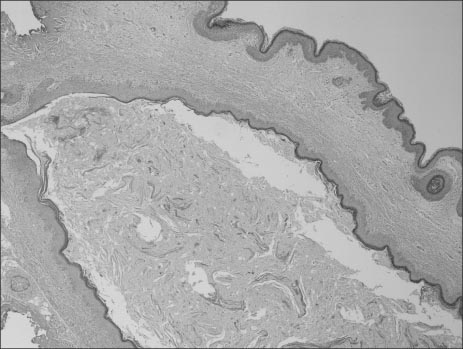

Fig. 2

Perineal ultrasonography reveals hypoechoic tubular mass without any communication between the mass and other organ.

Fig. 2 Perineal ultrasonography reveals hypoechoic tubular mass without any communication between the mass and other organ.